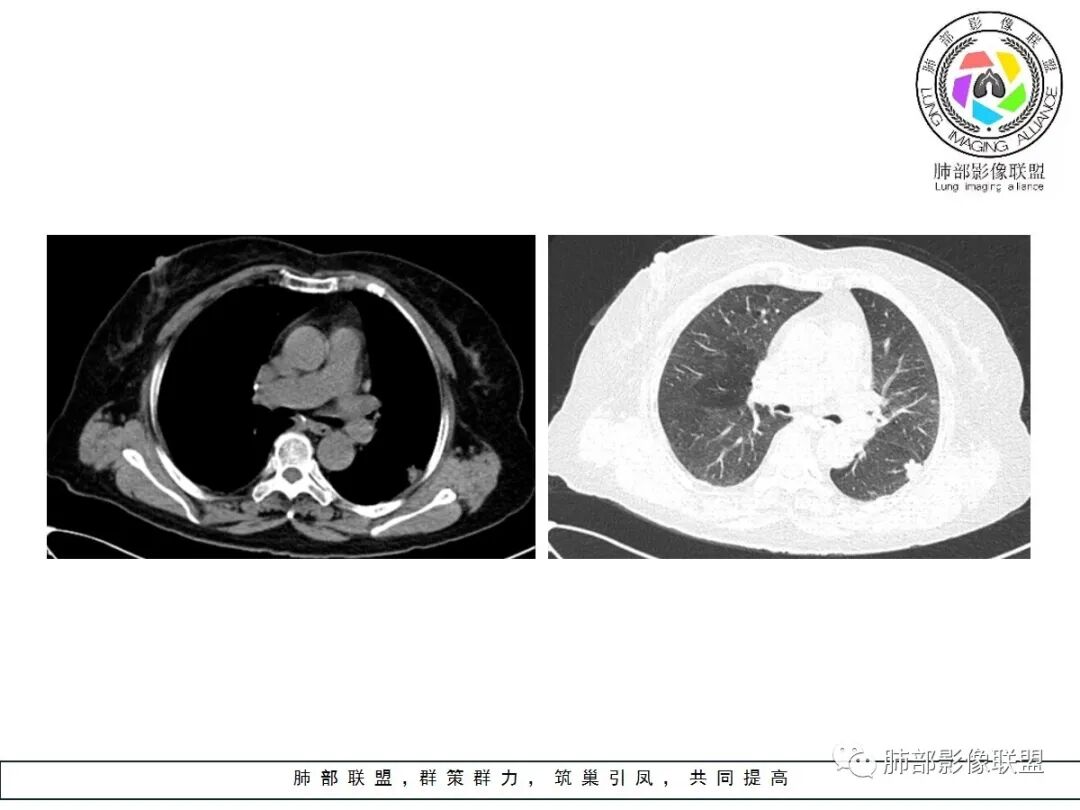

左肺下叶的不规则病灶,有恶性征象,有深分叶,病灶有支气管进入截断了,病灶里支气管扩张;良性征象有平直征,病灶强化明显,脂肪间隙存在,肉芽肿病变鉴别肌纤维母细胞瘤

老年女性,左肺下叶的不规则病灶,深分叶,病灶有支气管进入截断,血管集束,斜裂牵拉,但胸膜干净,有平直征,病灶强化明显,最后还是考虑恶性,鉴别隐球

左肺下叶背段胸膜下不规则结节,有良性征象:有平直、U形凹陷,胸膜下脂肪间隙清晰,明显强化;又有些恶性征象:有分叶,叶间胸膜牵拉。

有些纠结,还是考虑恶性(腺癌可能)> 炎性肉芽肿

临床无特殊。良性征像:冠状位方正,直边征,横断位略呈三角形,尖端指向肺门。恶性征像:小结节堆积样改变,轻度强化,增加20hu左右。横断位多分叶、毛刺。斜裂牵拉内收,胸膜被掀起伴局部少量积液,病灶底部似凸于胸膜外。腺癌与炎性肉芽肿病变的鉴别。强化方式及周边情况,结核可能小。收缩力很大,把腺癌放第一吧。

老年,实验室无异常,左肺结节,同胸膜宽基底相连,密度均,胸膜下脂肪存在,增强明显不均匀强化,考虑良性病变,炎性肉芽肿,结核,隐球。

良性征象(宽基底与胸膜相连,没有明显胸膜凹陷与微积液,收缩力较弱,仅仅叶间胸膜略凹陷,边缘平直,U形凹陷为主,结节较散,增强动脉期强化太明显)>恶性征象(局部略有膨隆,叶间胸膜略凹陷),可疑征象(图像不太好,支气管截断不确定,分叶征象不确定,也可能是散在结节的假象,脐凹征可疑),综合考虑良性结节可能大(隐球?结核?其他炎性结节?局部肺栓塞?)腺癌待排,临床简单,穿刺一下就OK。

左肺下叶胸膜下结节,边缘部分平直收缩部分膨隆,可疑脐凹征,邻近叶间裂稍牵拉,胸膜糊墙,增强扫描均匀强化,老年女性,良恶性征象都有,平扫密度似略偏高,先考虑良性,隐球菌?一般炎性肉芽肿?腺癌待排,老年人,警惕性提高一个级别,治疗后复查或穿刺活检。

左肺下叶前基底段斑片状影,边界清楚,增强强化15Hu,冠状位矢状位,边缘平直,胸膜下胸膜外脂肪间隙尚清楚,轻度强化,先抗炎,三个月复查。

有胸膜牵拉,老年女性,角蛋白19片段稍高,部分层面稍膨隆,呈球形,边界太清楚,恶性待排除,先抗炎,三个月复查。

老年女性,左肺下叶背段一节结影,近靠胸膜下,边缘分叶状,中等强化,强化均匀,周围肺叶见小结节影,考虑结核肉芽肿,不排除恶性结节,腺癌可能。